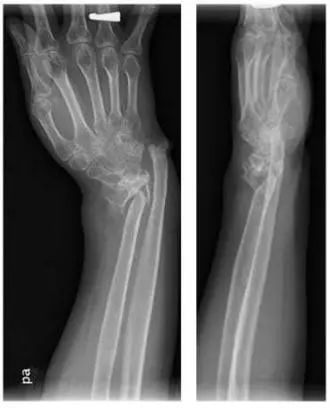

病例二

诊断:陈旧性桡骨远端骨不连,假关节形成,桡腕关节已融合。

治疗:骨不连假关节处植骨融合钢板内固定,尺骨短缩,单边外固定器固定。因桡腕关节已融合,故将单边外固定器反向应用。